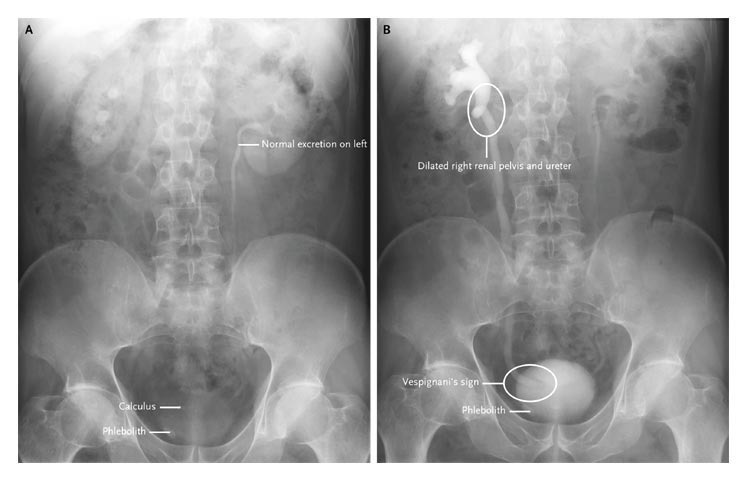

A 57-year-old man was referred to our hospital because of an acute onset of right flank pain. An intravenous urogram showed normal excretion from the left kidney, a calculus in the right pelvis, and a phlebolith in the right pelvis at 3 minutes after injection of the contrast material (Panel A).